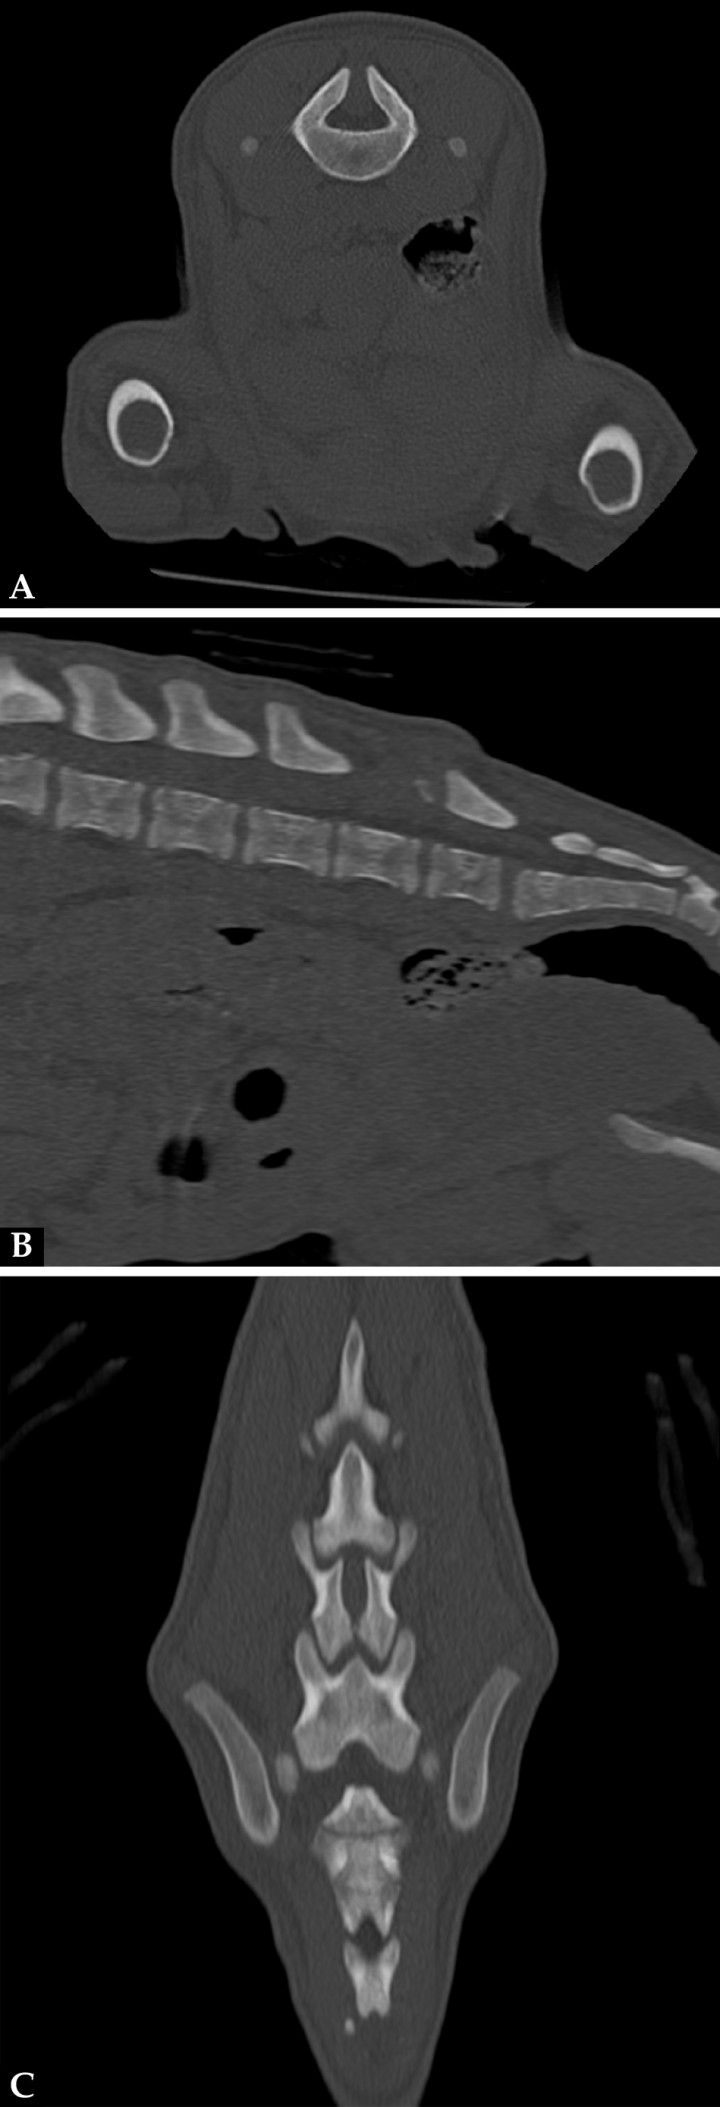

La mielografía podría ayudarnos a valorar el espacio subaracnoideo si sospechamos de un MC/MMC, aunque las técnicas de imagen avanzada, tomografía computarizada (TC) y resonancia magnética (RM) son las pruebas recomendadas si se sospecha de un defecto del tubo neural (DTN). Se realizó un estudio TC (General Electric Brivo CT385 Series de 16 cortes, Hangwei Medical Systems Co Ltd, Beijing, China, 16 cortes) sin y con contraste intravenoso, en el que se observó hipoplasia de la apófisis espinosa de L6 sin fusión de las láminas dorsales dejando un espacio abierto que comunicaba el canal vertebral y el tejido blando lumbar caudodorsal a L6 (Fig. 3). En las imágenes obtenidas en ventana de tejidos blandos tras administración de contraste se apreció el paso por el defecto espinal de tejido del canal vertebral con atenuación tejido blando y realce periférico, hasta el tejido blando dorsal a L6-7 (Fig. 4).

Figura 3

Imágenes de TC en ventana de hueso. (A) Plano transversal. (B) Reconstrucción en plano sagital. (C) Reconstrucción en plano dorsal. Hipoplasia de la apófisis espinosa de L6 sin fusión de las láminas dorsales dejando un espacio abierto que comunica el canal vertebral y el tejido blando lumbar caudodorsal a L6